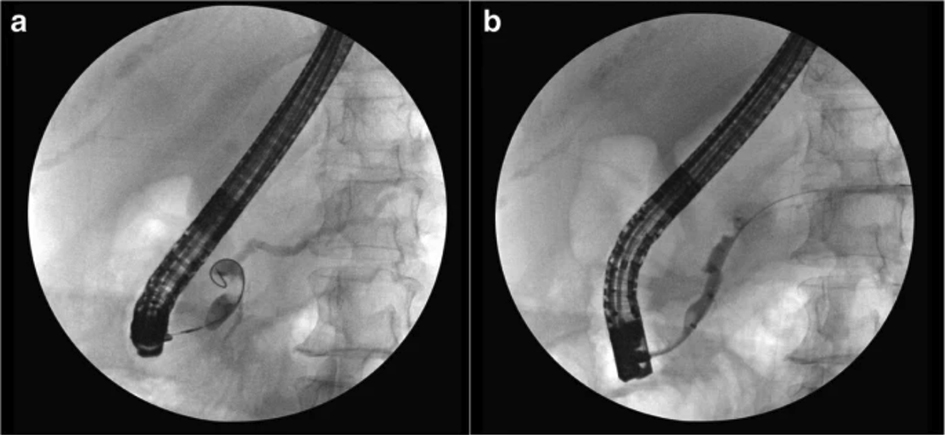

(III) Approach via the puncture channel

This refers to the operation that meets the super minimally invasive requirements by entering the lacunar or lumen through the puncture route. For instance, laparoscopic, thoracoscopic, arthroscopic-aided operations, related operations after body surface guided puncture bile duct, gallbladder, related operations conducted after ultrasonic endoscopic guided puncture chambers, etc. (figure 2.3).

FIG. 2.3 — SMIS through a puncture channel.